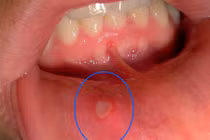

(Kiến Thức) - Nhiều người thường gặp hiện tượng chốc mép, loét miệng, nẻ môi dẫn đến chảy máu khi mùa Đông đến. Hiện tượng này không chỉ ảnh hưởng đến thẩm mỹ mà còn gây ra không ít khó khăn cho việc ăn uống hàng ngày của bạn.

Nguyên nhân của triệu chứng chốc mép ngoài thời tiết hanh khô, cơ thể thượng Hỏa thì còn do thiếu vitamin B2 trầm trọng.